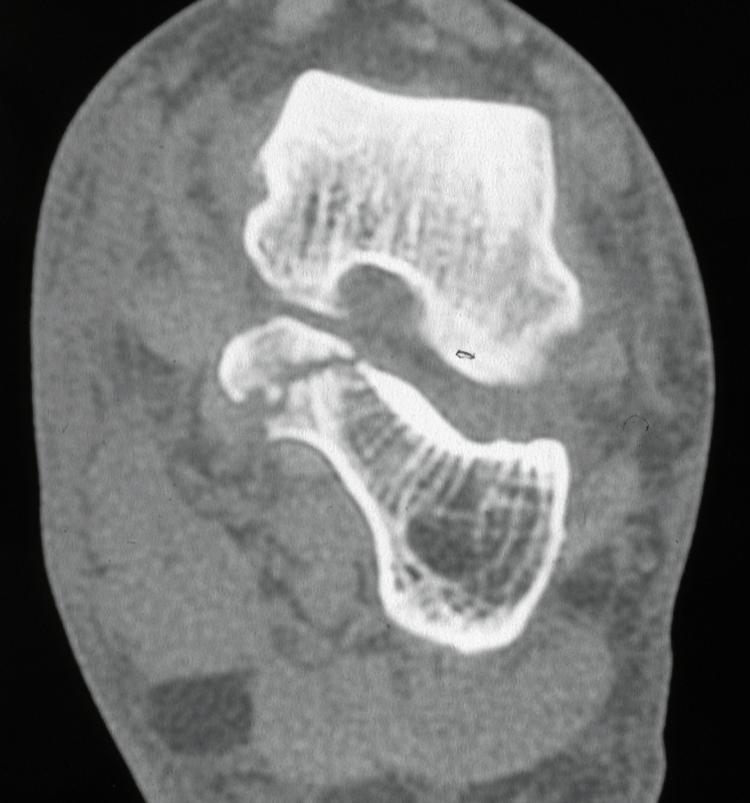

Sustentaculum tali: The sustentaculum tali is the antero-medial shelf of the calcaneum which provides structural support for the talus and includes the middle facet of the subtalar joint. The spring ligament, tibiocalcaneal and medial talocalcaneal ligaments attach to it and FHL runs in a groove under it. Isolated fractures of the sustentaculum tali are rare and are usually associated with a fall or high energy trauma, combined with a twisting movement. The patient may complain of medial hindfoot pain and have an antalgic gait. Examination will show tenderness 2-3cm below the medial malleolus.

Passive extension of the great toe may produce medial hindfoot pain, due to irritation of FHL, and subtalar joint movement will be painful and limited. They can be difficult fractures to see on standard views of the foot and are best seen on axial views of the calcaneum and then a CT scan (Figure 6 &7). It used to be thought these were extra-articular fractures which could be treated non-weight-bearing for six weeks and with early range of movement exercises, as the fractures are usually minimally displaced. It is now thought best to reduce and internally fix them. These fractures can also occur in conjunction with other trauma, such as a subtalar joint dislocation.

Fig 6.png

Figure 6: Lateral X-ray sustentaculum tali fracture.

Fig 7.jpg

Figure 7: CT showing sustentaculum tali fracture.